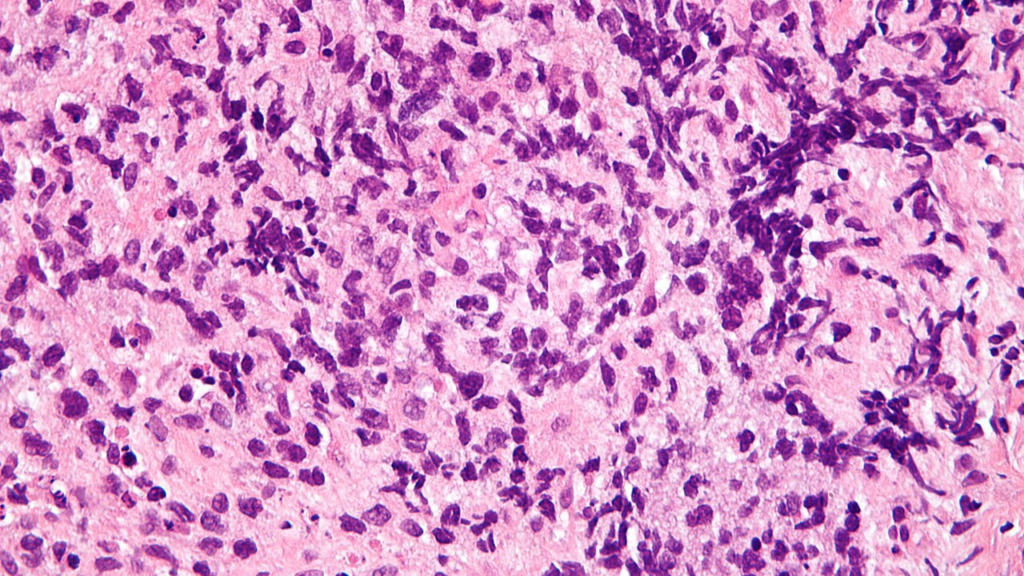

Lorsque l’origine des adénopathies médiastinales reste incertaine, un prélèvement peut être nécessaire. L’analyse histologique des tissus permet d’identifier avec précision la nature de l’atteinte.

Plusieurs techniques existent pour accéder aux ganglions médiastinaux. La fibroscopie bronchique avec ponction transbronchique guidée par échographie est aujourd’hui largement utilisée. Elle permet de prélever des échantillons de manière relativement peu invasive.

Dans certains cas, une médiastinoscopie peut être indiquée. Cette intervention chirurgicale consiste à introduire un instrument dans le médiastin pour visualiser et biopsier les ganglions. Bien que plus invasive, elle offre une grande précision diagnostique.

Le choix de la technique dépend de plusieurs facteurs, notamment de la localisation des ganglions et de l’état général du patient. L’objectif est toujours d’obtenir un diagnostic fiable tout en minimisant les risques.